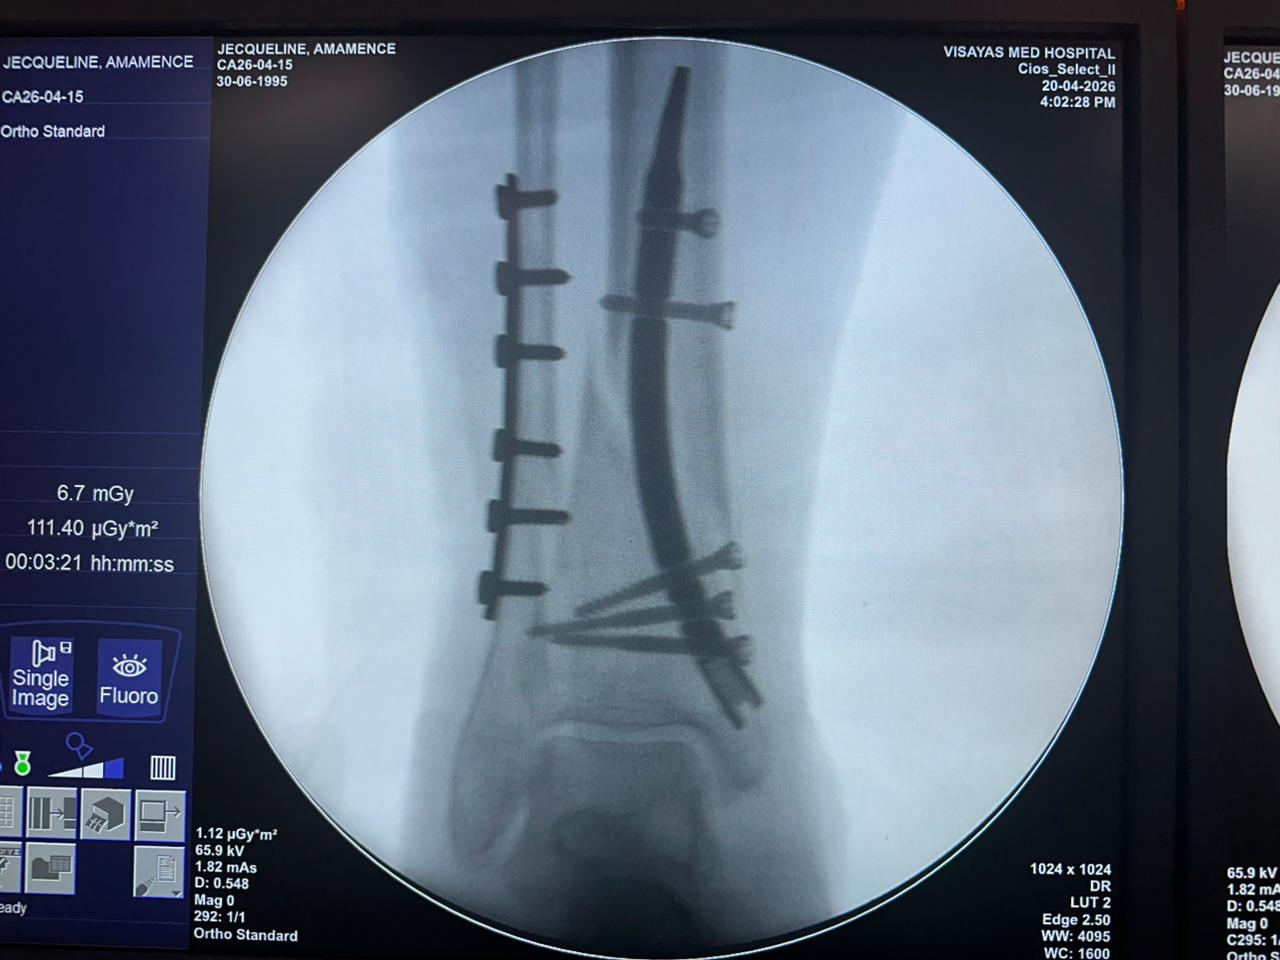

Étude de cas sur la fixation d'un clou tibial distal avec support de plaque fibulaire

Radioscopie peropératoire de l'arceau, vues AP et latérales

Ce cas concernait une fixation tibiale distale à l’aide d’un clou tibial distal intramédullaire. La radioscopie peropératoire a confirmé la position du clou, des vis de verrouillage distales et de la fixation par plaque fibulaire.